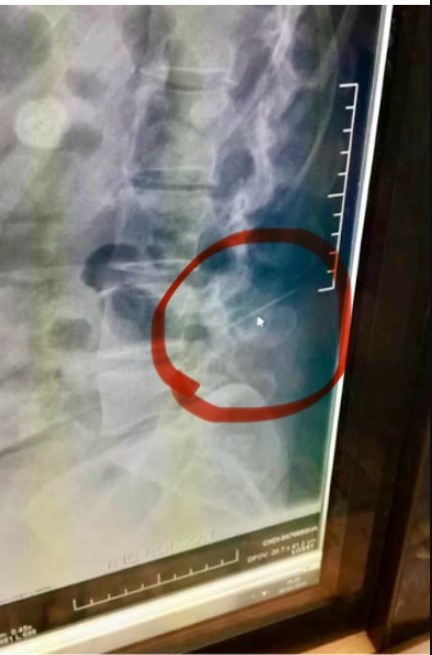

அந்த எக்ஸ்ரே பயங்கர உண்மை ஒன்றை வெளிக்கொணர்ந்தது. ஆம், அவரது முதுகெலும்புக்குள் உடைந்த ஒரு ஊசியின் ஒரு பெரிய துண்டு இருப்பது தெரியவந்தது.

அந்த ஊசியுடனேயே அவர் பல ஆண்டுகளாக வாழ்ந்துவந்துள்ளார். அத்துடன், அந்த ஊசிதான் தனது தோள் மற்றும் கால்வலிக்கும் காரணம் என்பது அவருக்கு பிறகுதான் தெரியவந்துள்ளது.